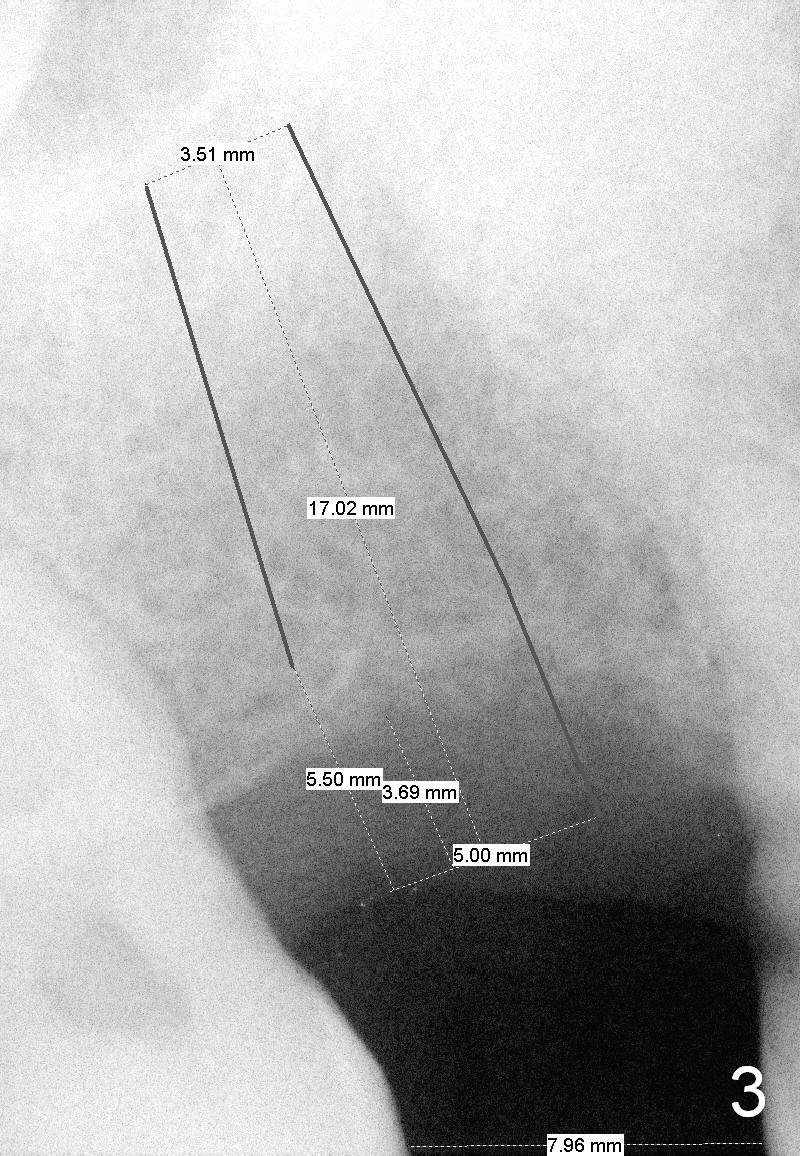

Although the bone height allows a 14 mm long implant, the initial depth of osteotomy is 10 mm. Prepare the SM cassette. The advantage of using 4 mm shorter drill is that it is easy to change trajectory if it is not right, determined by the 1st intraop PA.

If the bone density is found to be low while using the 2 mm pilot drill, use bone expanders until 2 sizes smaller than the final diameter (Fig.3,4). Use the 5 mm implant positioner to preliminarily determine the diameter of the implant. Place the initial osteotomy slightly palatal. Check whether the osteotomy shifts buccally after each step of bone expansion or drilling.